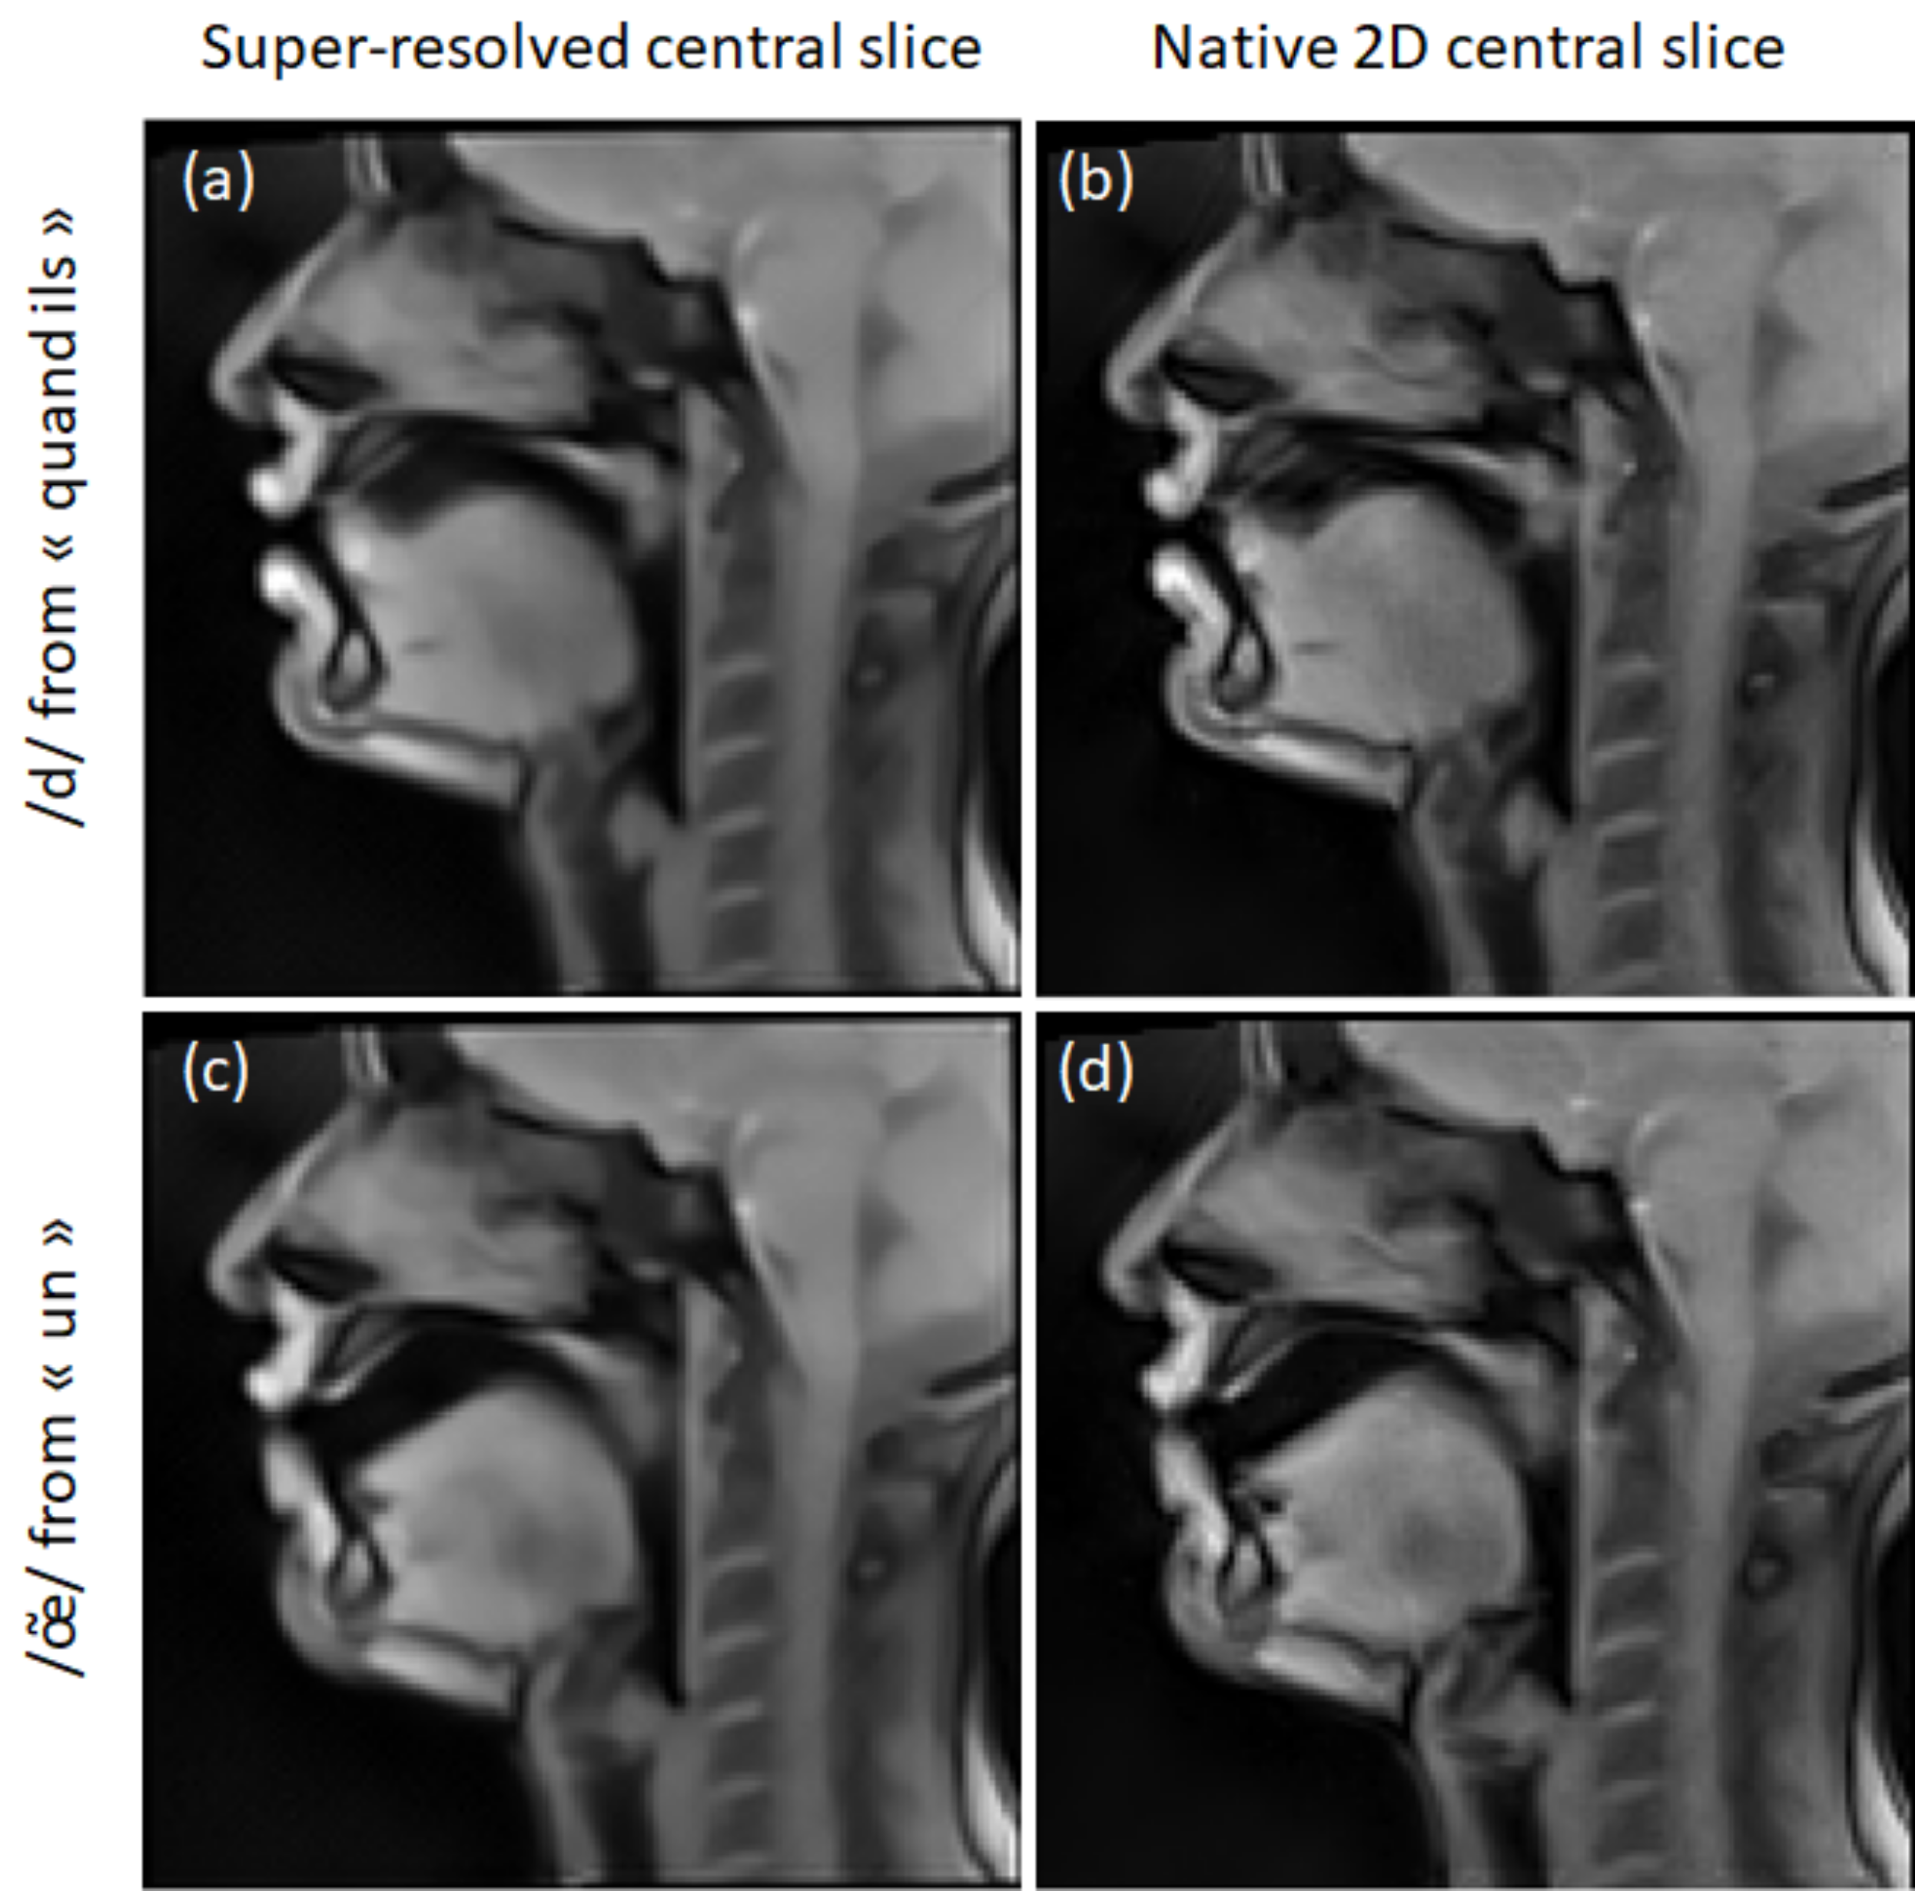

3.2. Super-Resolution